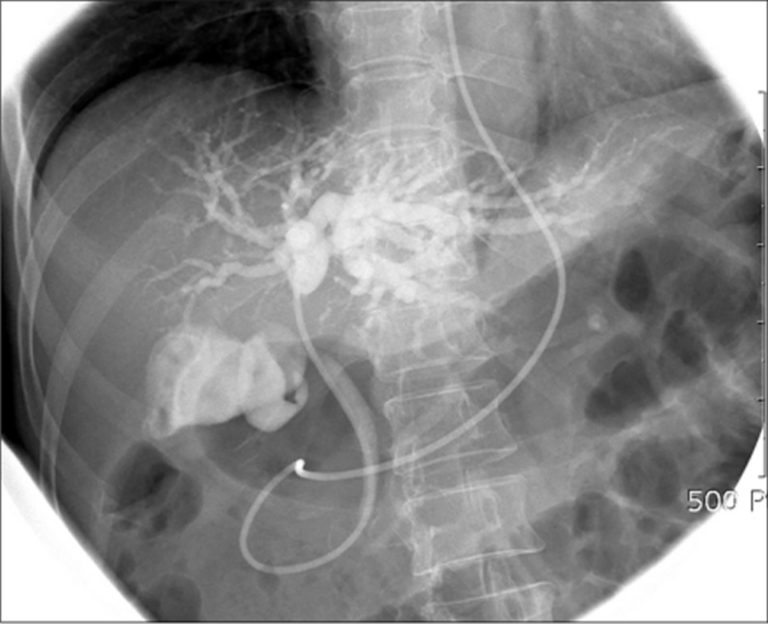

PPT ERCP & Fluoro Quiz PowerPoint Presentation ID6818168 Ercp Indications And Contraindications Visceral perforation, suboptimal anesthesia support, and partially or fully. the indications of ercp in pregnancy include biliary pancreatitis, symptomatic choledocholithiasis, cholangitis, and. contraindications to ercp are relative: the appropriate use of endoscopic retrograde cholangiopancreatography (ercp), and avoidance of this procedure when it is. despite the near ubiquitous access to advanced radiology and endoscopic ultrasound (eus) in. Ercp Indications And Contraindications.